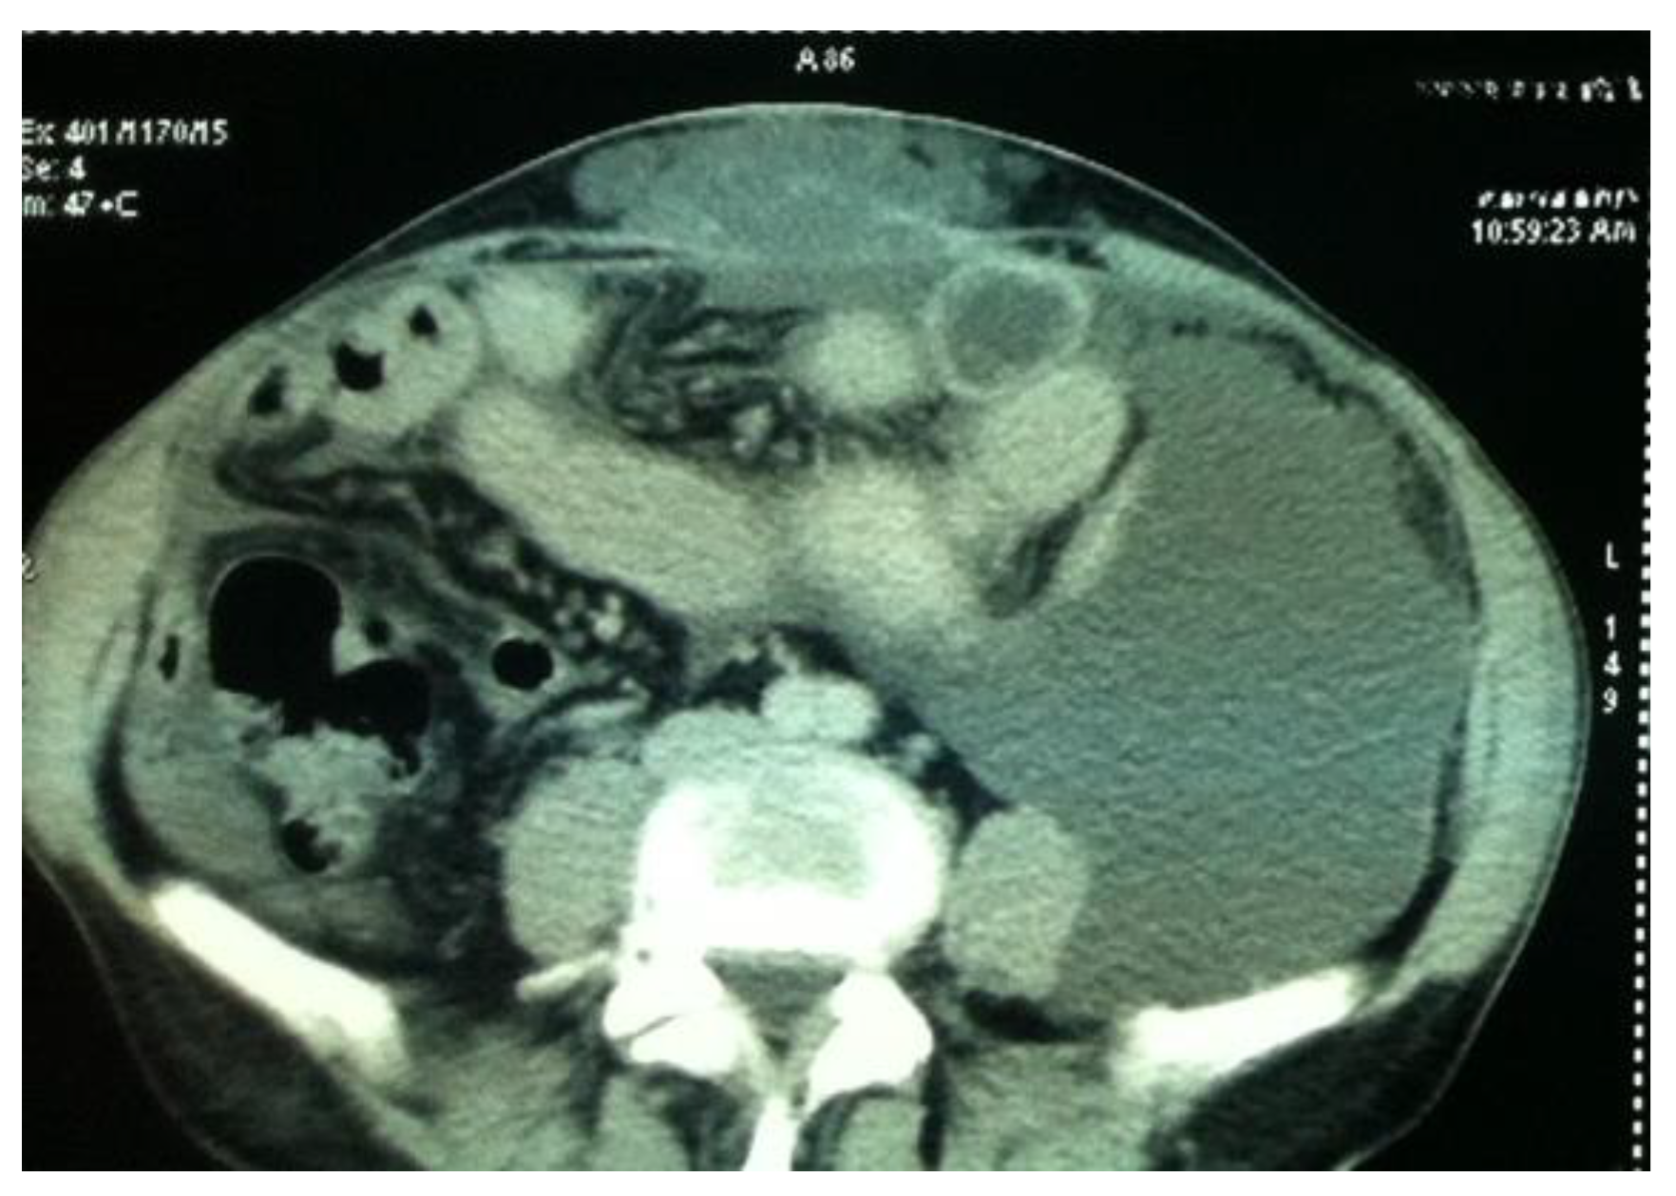

2.2. Clinical and Imaging Evaluation